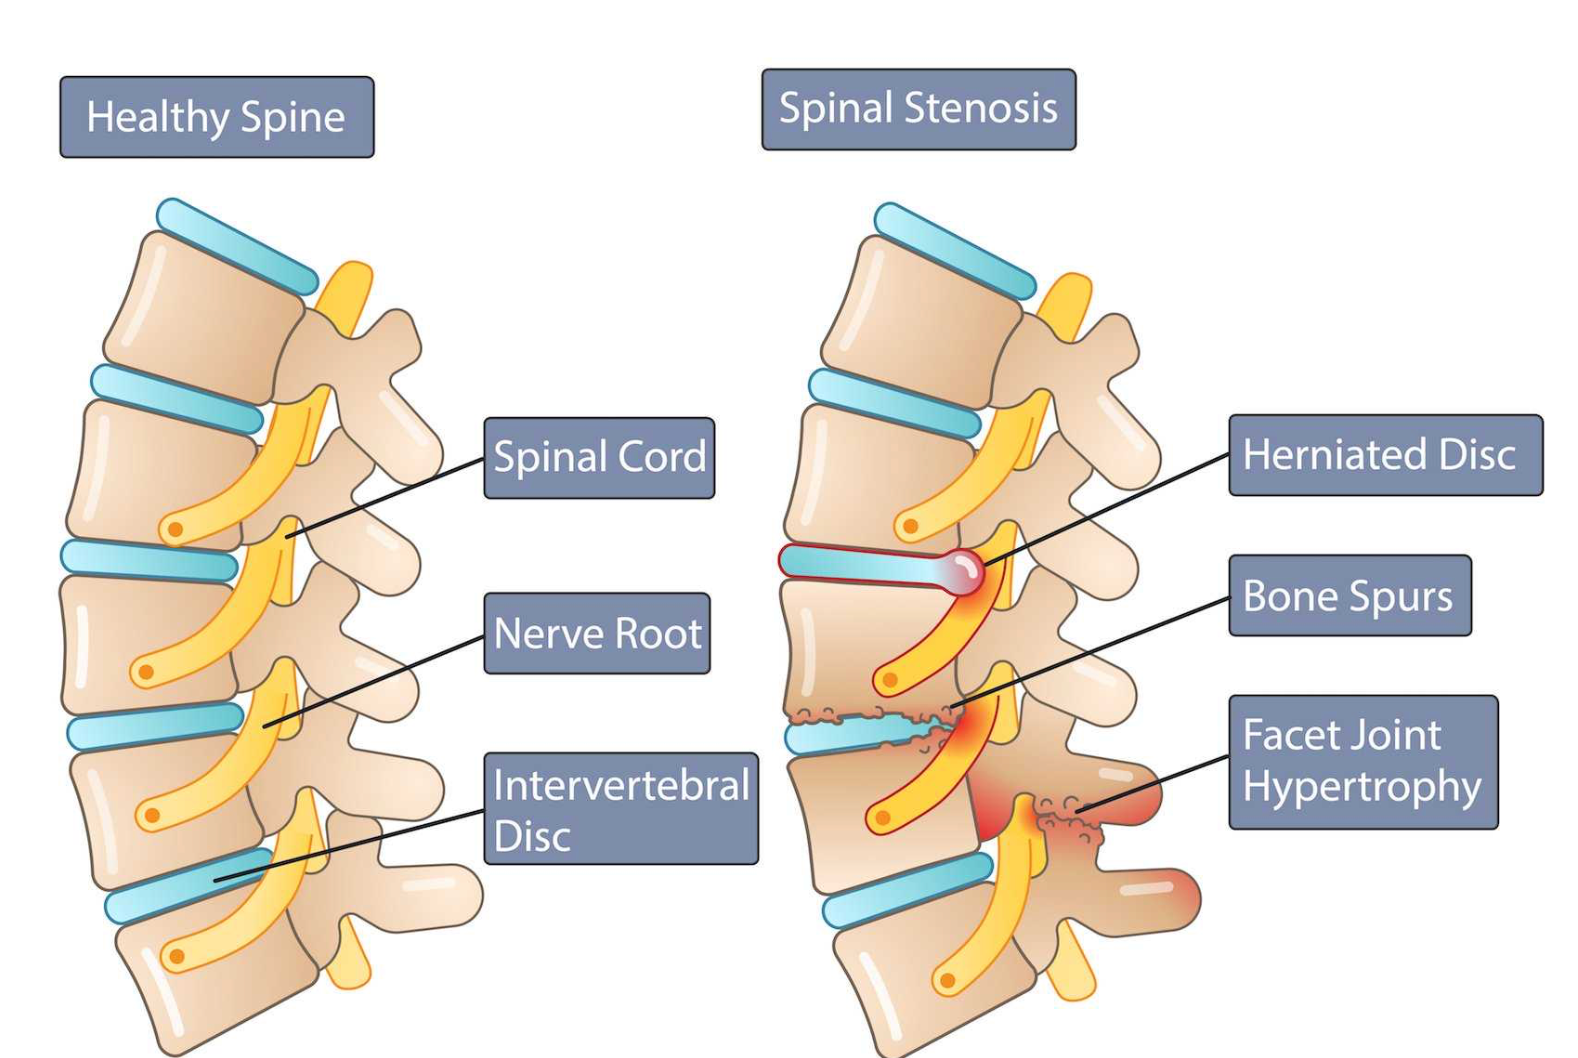

Conditions Treated with MIS TLIF

- Lumbar spondylolisthesis

- Degenerative disc disease

- Recurrent disc herniation

- Lumbar canal stenosis with instability

- Facet joint arthritis

MIS TLIF (Minimally Invasive Transforaminal Lumbar Interbody Fusion) is a modern spine surgery technique used to stabilize the lumbar spine and relieve nerve compression while minimizing muscle injury.

MIS TLIF is recommended when spinal instability and nerve compression coexist and conservative treatments have failed.